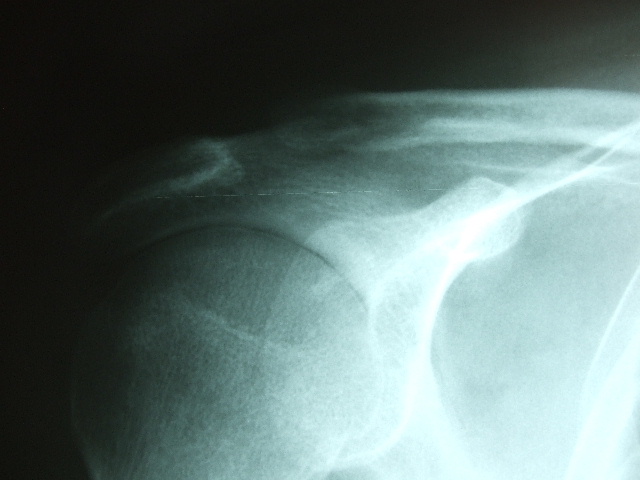

Fractura impactada de húmero .

Fractura de húmero.

Fractura compleja de húmero.